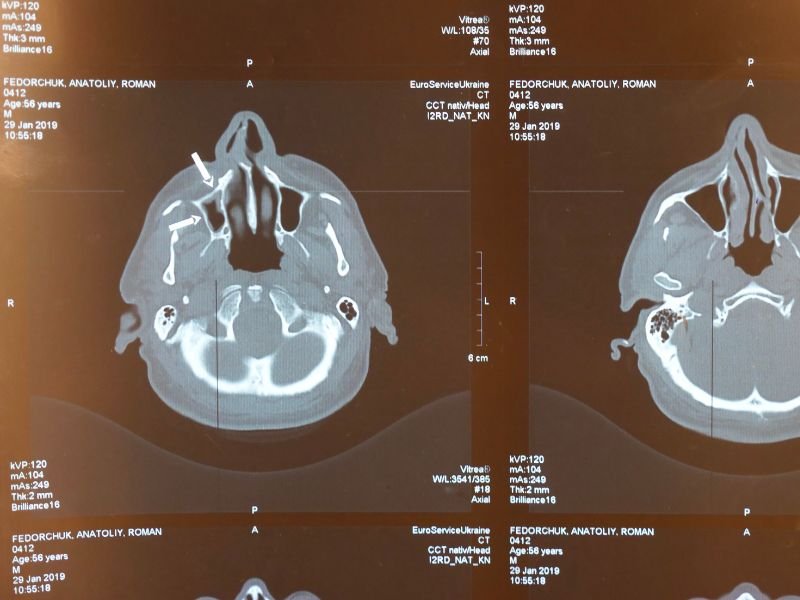

Tratamento Avançado para Enxaqueca em Tubarão A enxaqueca é uma condição neurológica que afeta milhões de pessoas em todo o mundo. Em Tubarão, o tratamento avançado para enxaqueca tem se tornado uma prioridade para muitos